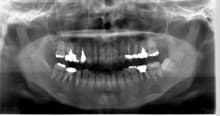

歯周病専門治療

歯周病専門治療 20代 女性

皆さんは体調崩していませんか?わたしはおかげさまで今日もばっちりでした さて、それでは本日も歯周病治療の症例をご紹介してまいります 年齢は20代後半の女性の方です。 治療している歯も…